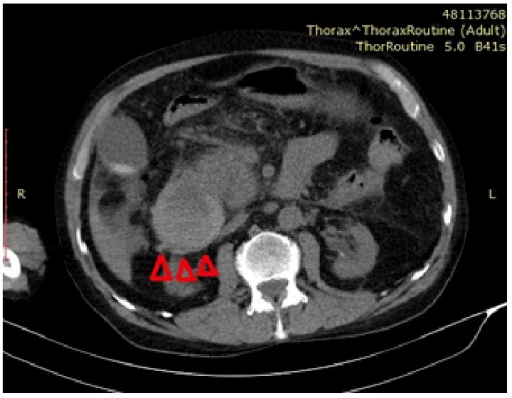

A Lethal Complication of Endoscopic Therapy: Duodenal Intramural Hematoma. Calhan T, Sahin A, Kahraman R, Soydaş B, Tosun A, Cebeci E - Case reports in gastrointestinal medicine (2015)